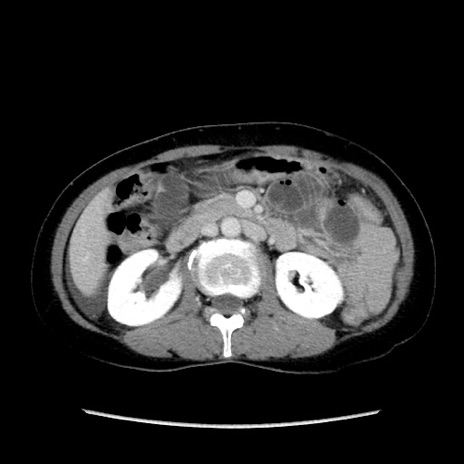

症例32(横断像)

【症例】40歳代 女性

【主訴】上腹部痛、嘔気・嘔吐

【現病歴】約9時間前頃から急に上腹部痛、嘔気、嘔吐が出現。改善しないため救急要請。

【既往歴】子宮頚癌(広汎子宮全摘術、放射線療法)、腸閉塞

【身体所見】腹部:平坦、軟、腸雑音亢進、上腹部を中心に腹部全体に圧痛あり。

【データ】WBC 8400、CRP 0.03